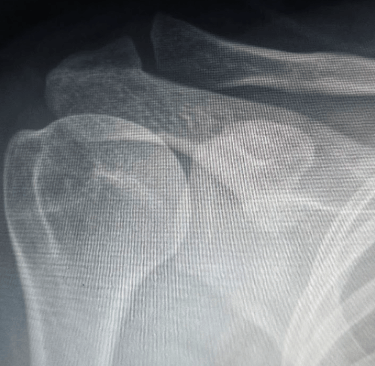

• Fracturas: Golpes o caídas pueden ocasionar fracturas en la clavícula, el húmero o la escápula, resultando en dolor severo y limitación de movimiento.

Para identificar la causa exacta del dolor de hombro, es necesario realizar una evaluación médica completa. El especialista llevará a cabo una exploración física para evaluar el rango de movimiento, la fuerza y la estabilidad de la articulación.

Además, pueden solicitarse estudios de imagen para observar el estado de los huesos, los músculos y los tejidos blandos. En algunos casos, se requieren pruebas de laboratorio para descartar enfermedades inflamatorias o infecciones que puedan estar afectando la articulación.